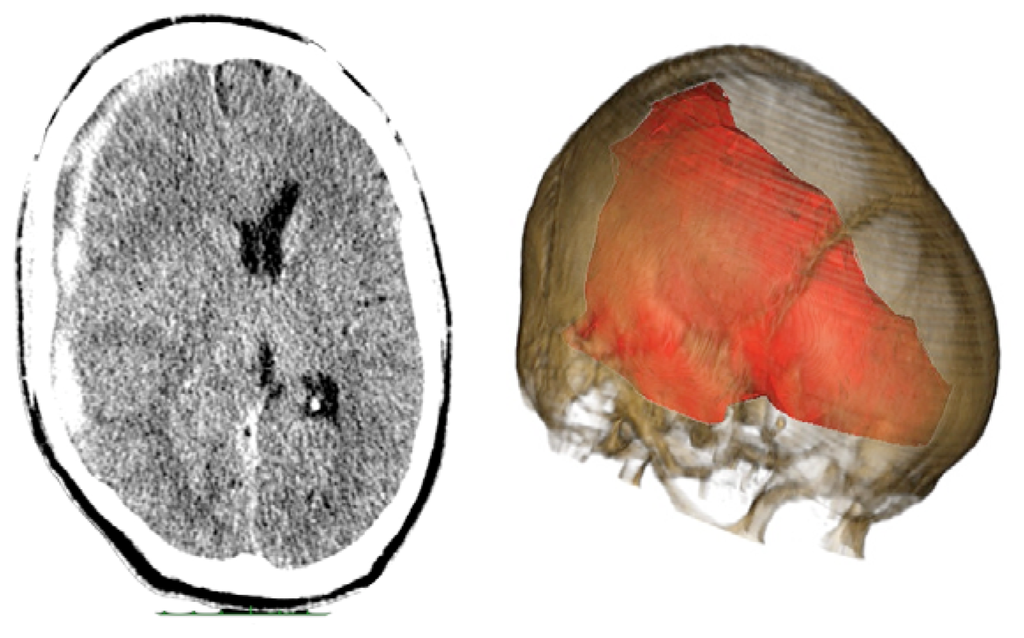

Case 3-Contusional Hematomas (See Figures 5 and 6 for the details)

A 61-year-old alcoholic man was a patient who was hit by a motorcycle. Initially, he was alert and fully oriented. In the emergency department, the patient became disoriented; the examination revealed no signs of injury, and coagulation studies were normal. Within 30 min after the initial evaluation, his neurologic status deteriorated (GCS of 8). The CT scan revealed an acute right-sided post-traumatic intracranial parietal contusion containing an intraparenchymal hematoma, and acute subarachnoid hemorrhage in the right sylvian fissure. The patient underwent intubation and referred promptly to the operating room. Through the interpretation of the images 3D, we identify the best entry point for an endoscopic approach through a burr-hole. The patient had adequate recovery and was discharged seven days after surgery.

Contusional Hematomas

Contusional hematomas were operated with endoscopic technique already described by several authors for spontaneous intraparenchymal hematoma [3,30–32]. The observation of 3D images enabled us to choose the best location (far from eloquent areas and with less brain tissue between the hematoma and the brain surface), to insert the “neuroport”. The neuroport is a canula used to dissect the brain tissue till the hematoma causing less injury to the adjacent brain tissue [3,30–32].

The resection of the hematoma followed the same line of the spontaneous hematomas [3,30–32]. All hematoma were resected satisfactorily. However, despite achieving adequate decompression, three patients had residual hematoma on the control CT scan. None required reoperation. There was no difference or specific difficulty. As seen in Table 1, only one patient, who had also a contralateral acute subdural hematoma had a bad outcome (GOS of 3).